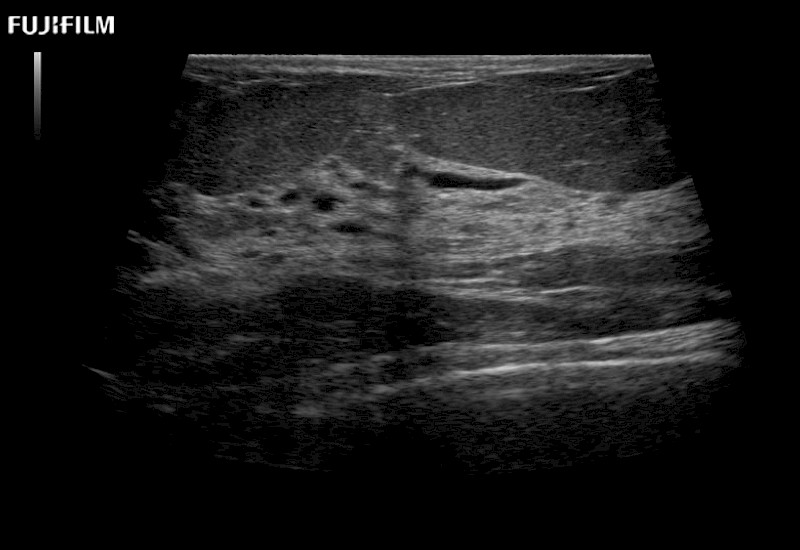

Extraordinary high-resolution digital imaging

for use during open and laparoscopic procedures: Tumor localization & staging, Ablation, Resection, Biopsy, Transplant, Abdominal exploration, Robotic surgery

Multi-Parametric imaging modalities